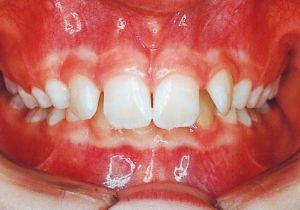

Age at Initial Visit: 11years 3month, Male / Deep bite. Protruding upper bite, Spaced arch.

1 Initial Visit 9-3-’91

Class II deep bite in mixed dentition. A significantly large overjet and a spaced arch are observed. The cephalometric X-ray shows that the anteroposterior displacement of the maxilla and mandible is not particularly large (ANB 5°), but the nasal floor is elevated anteriorly, providing evidence supporting a history of thumb sucking. The skeletal form shows a relatively slight mandibular body deficiency, but the mandibular ramus is adequately sized and appears likely to develop sufficiently. The use of headgear was planned to suppress maxillary anterior growth and achieve relative mandibular advancement. Treatment was performed without extraction, assuming continuity until the permanent dentition stage.